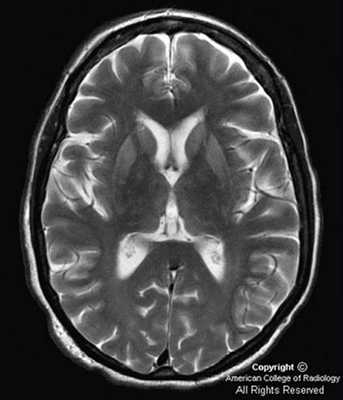

При проведении МРТ головного мозга в Т2-режиме определяется так называемый «симптом медовых сот» - участки повышенного сигнала, исходящие от подкорковых ганглиев и таламуса. Зачастую выявляются признаки атрофических изменений мозжечка и коры головного мозга, расширение желудочков и боковых цистерн мозга. ПЭТ диагностирует зоны пониженного метаболизма, локализующиеся в подкорковых ядрах, полушариях мозжечка и коре мозга.

До недавнего времени «золотым стандартом» верификации диагноза БКЯ являлась биопсия головного мозга, позволяющая выявить характерные изменения в мозговой ткани в виде мелких вакуолей в телах нейронов, из-за чего ткань мозга приобретает губчатый вид, пролиферации клеток глии при отсутствии признаков воспаления. При электронной микроскопии возможно обнаружение прионных палочек, являющихся патогномоничным признаком заболевания. Указанные морфологические изменения отмечаются в коре головного мозга, базальных ганглиях, мозжечке и верхних отделах ствола мозга. Однако в случаях БКЯ биопсия мозга не нашла широкого применения в клинической практике из-за инвазивности метода, сложности санитарной обработки оборудования и утилизации биоматериалов, связанных с высокой устойчивостью прионов, а также вследствие небольшого объема биоптата мозговой ткани, что может быть причиной ложноотрицательных результатов морфологического и иммуногистохимического исследования. Однако в настоящее все больше распространена МРТ диагностика данного заболевания, по причине выявления специфических изменений, наиболее информативными являются последовательность DWI.

На диффузионно-взвешенной (DWI) магнитно-резонансной томографии (МРТ) головного мозга выявляются аномальные билатеральные гиперинтенсивные сигналы на Т2-взвешенных изображениях (симптом «медовых сот») преимущественно в области головок хвостатых ядер, таламуса, отмечается атрофия коры больших полушарий и мозжечка [6].

- На МРТ можно выявить признаки атрофических изменений в мозжечке и коре мозга (синдром «медовых сот»), расширение желудочков. От подкорковых структур и таламуса иногда улавливаются участки с повышенным сигналом.